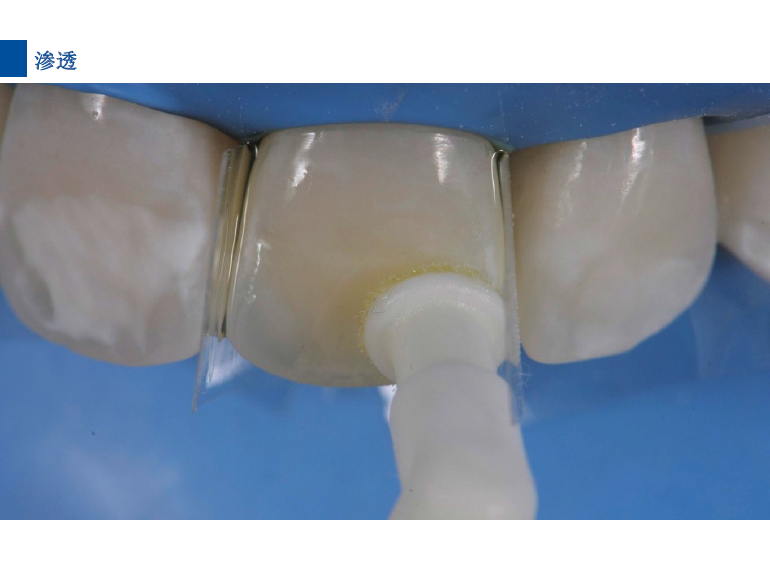

6、将配套唇颊面龋损治疗的注射头装在含爱康渗透树脂Icon-Infiltrant注射器上。

7、旋转注射器柄部将足量材料涂布于已被酸蚀的龋损表面之上,等待3分钟,并用棉球去除多余材料。不要在牙椅照明灯直射下在前牙唇面涂布树脂。)

8、光照40秒

9、将一新的注射头装在含爱康渗透树脂Icon-Infiltrant的注射器上,重复步骤7-8.等待1分钟,光照40秒。